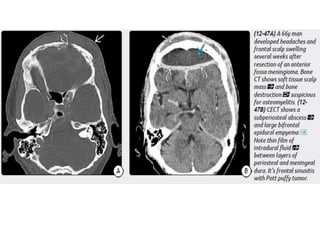

Imaging

NECT scans may be normal or show a hypodense extraaxial collection

that demonstrates peripheral enhancement on CECT.

Bone CT should be evaluated for signs of sinusitis and otomastoiditis.

MR is the procedure of choice for evaluating potential empyemas. T1

scans show an extraaxial collection that is mildly hyperintense relative to

CSF.

SDEs are typically crescentic and lie over the cerebral hemisphere. SDEs

often extend into the interhemispheric fissure but do not cross the midline.

EDEs are biconvex and usually more focal than SDEs. EDEs may cross

the midline, confirming their epidural location